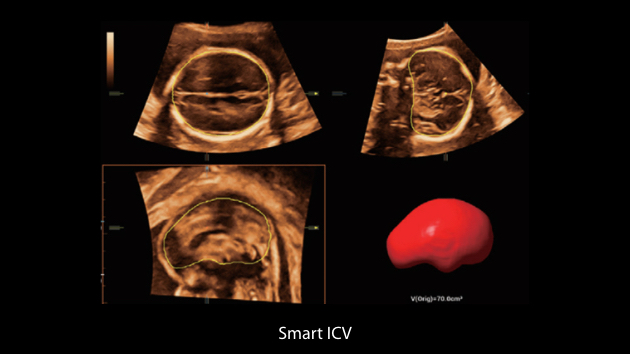

The Nuewa I9 Elite Edition, dedicatedly designed for women and neonatal healthcare, providing an innovative experience from inside out. These innovations are developed based on in-depth insights into complex clinical scenarios, providing accurate and timely answers as well as outstanding efficiency and remarkable user experience